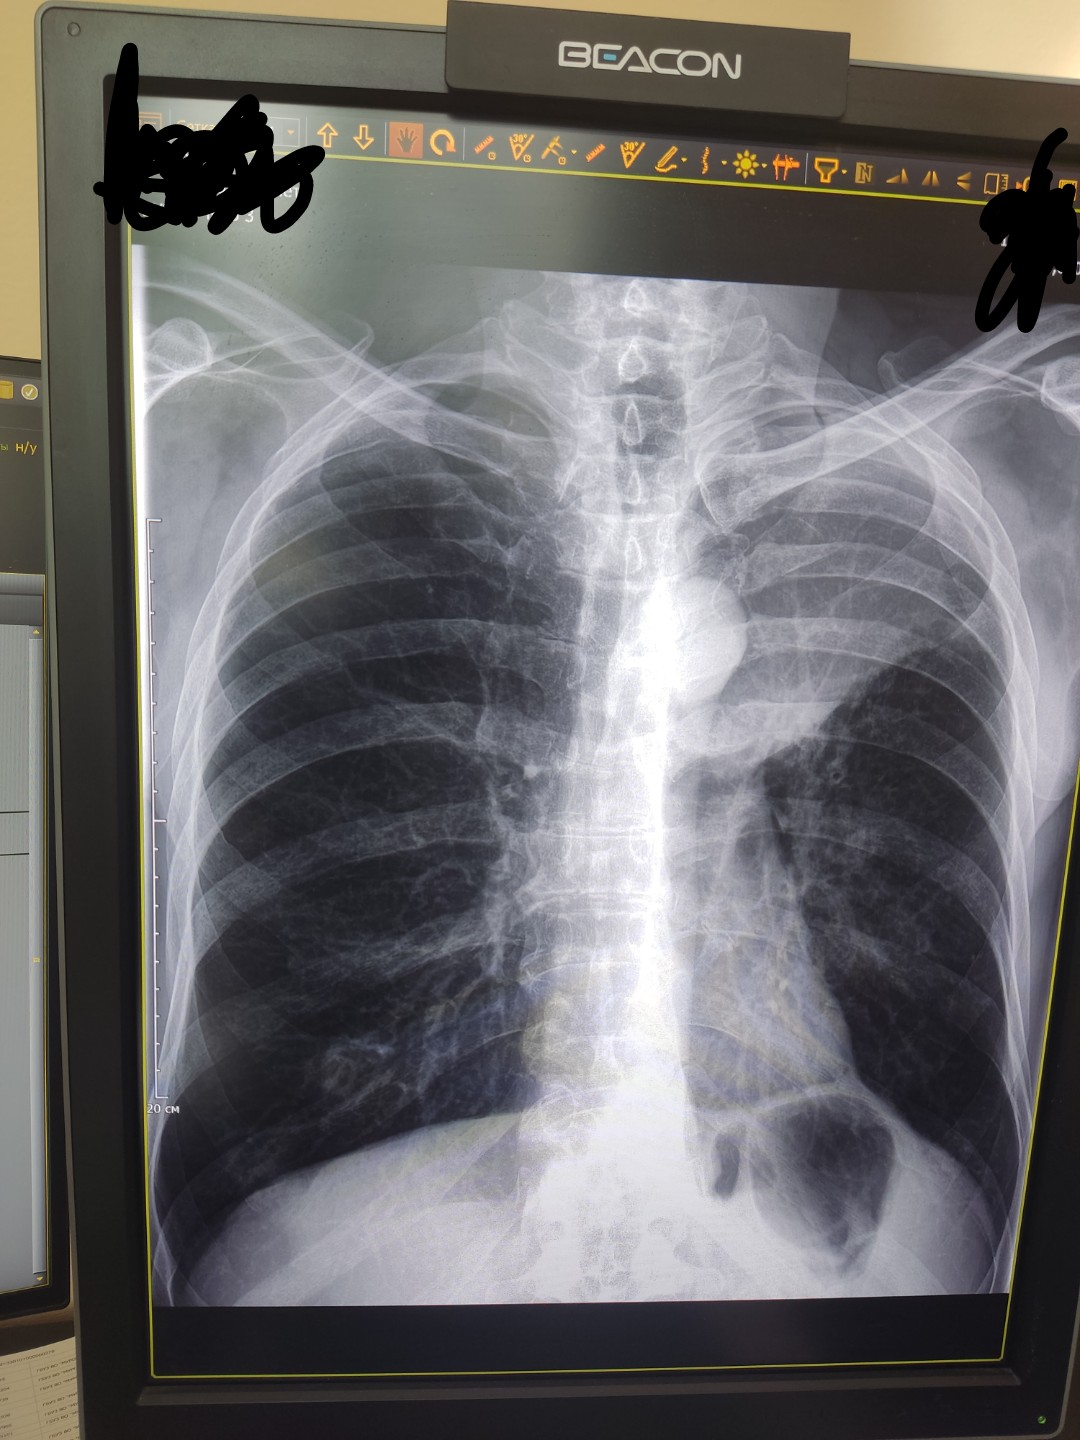

Рентгеновские снимки опухоли Панкоста